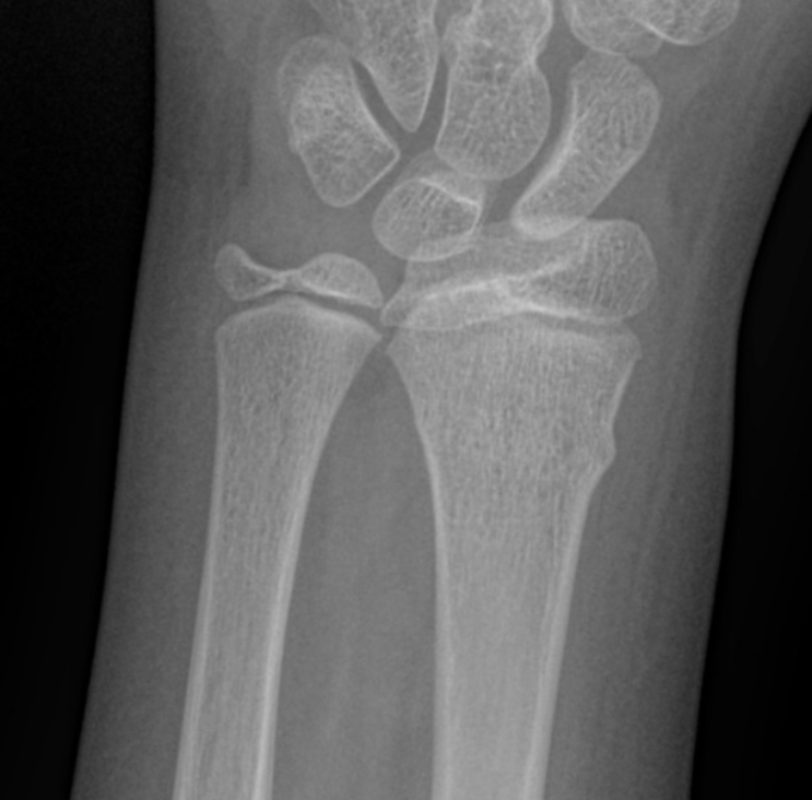

After your thorough history and physical exam including neurovascular status, you obtain radiographs of your patient's injured extremity. In addition to the wrist and forearm, you also obtain radiographs of the elbow on the affected side, which were normal.

Figure: AP and lateral radiographs. Image courtesy of Pediatric Imaging. Pediatricimaging.org. Used under the creative commons license.

The radiographs show distal radius and ulna buckle or torus fractures. As these are stable fractures that do not involve the growth plate, you apply a splint to immobilize the arm and provide a referral to the orthopedic clinic next week. The patient feels better after splint placement and receiving a dose of ibuprofen.